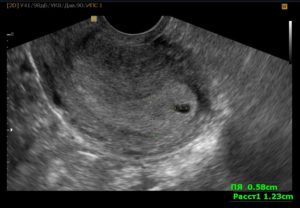

Полип – образование доброкачественной природы, которое состоит из увеличенного слоя эндометрия и находится в маточной полости или цервикальном канале. Новообразование может иметь разные размеры, варьирующиеся от 1 мм до 5-6 см, и «комплектацию»: вырост эндометрия может быть одиночным и диффузным. В последнем случае фиксируется множественные очаги наростов.

Полип эндометрия на УЗИ проявляется как достаточно четкая цилиндрическая структура белесоватого оттенка.

Как говорят специалисты, полип — гиперэхогенное образование. Что это значит? Нарост имеет плотную структуру, настолько, что выделяется на фоне стенок матки светлым пятном. Ультразвук поглощается жидкостью и полостями, они на снимке темные. Чем плотнее ткани, тем более светлыми будут, например, кости ярко-белые.

Полип формируется из собственных клеток эндометрия. Причем таким образом, что содержит основу из фиброзных волокон, которые обладают высокой плотностью и заполненные промежутки железистыми клетками. Поэтому на УЗИ полип выглядит вытянутым светлым пятном цилиндрическое или пальцеобразное. Иногда можно отличить тонкую ножку образования.